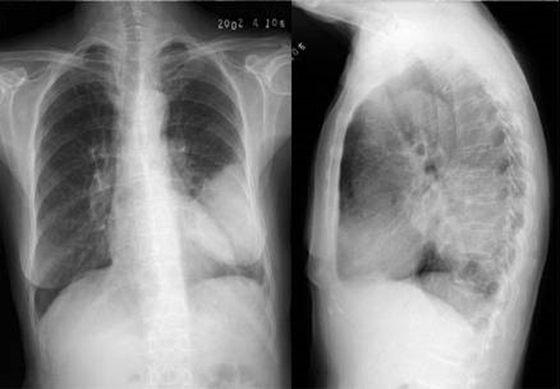

04卷-3.病史:男性,53歲,咳嗽、體重減輕4個(gè)月。診斷

A.左下肺炎

B.左下包裹性積液

C.左下肺癌

D.左下肺結(jié)核

題目解析:【該題針對(duì)“ X線-肺癌 ”知識(shí)點(diǎn)進(jìn)行考核】